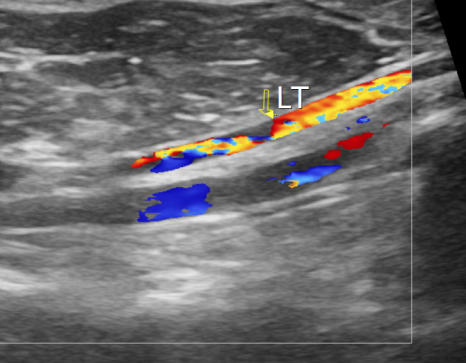

복부 대동맥 초음파 검사 / 출처: 24시온숲동물의료센터

복부 대동맥 초음파 검사

복부 대동맥 분지부와 대퇴동맥 내에서 국소적 혈전(폐색) 이 관찰되었습니다.

이러한 결과는 좌심방압 상승과 혈류의 와류로 인해 혈전이 형성된 전형적인 ATE의 기저 질환 패턴과 일치했습니다.